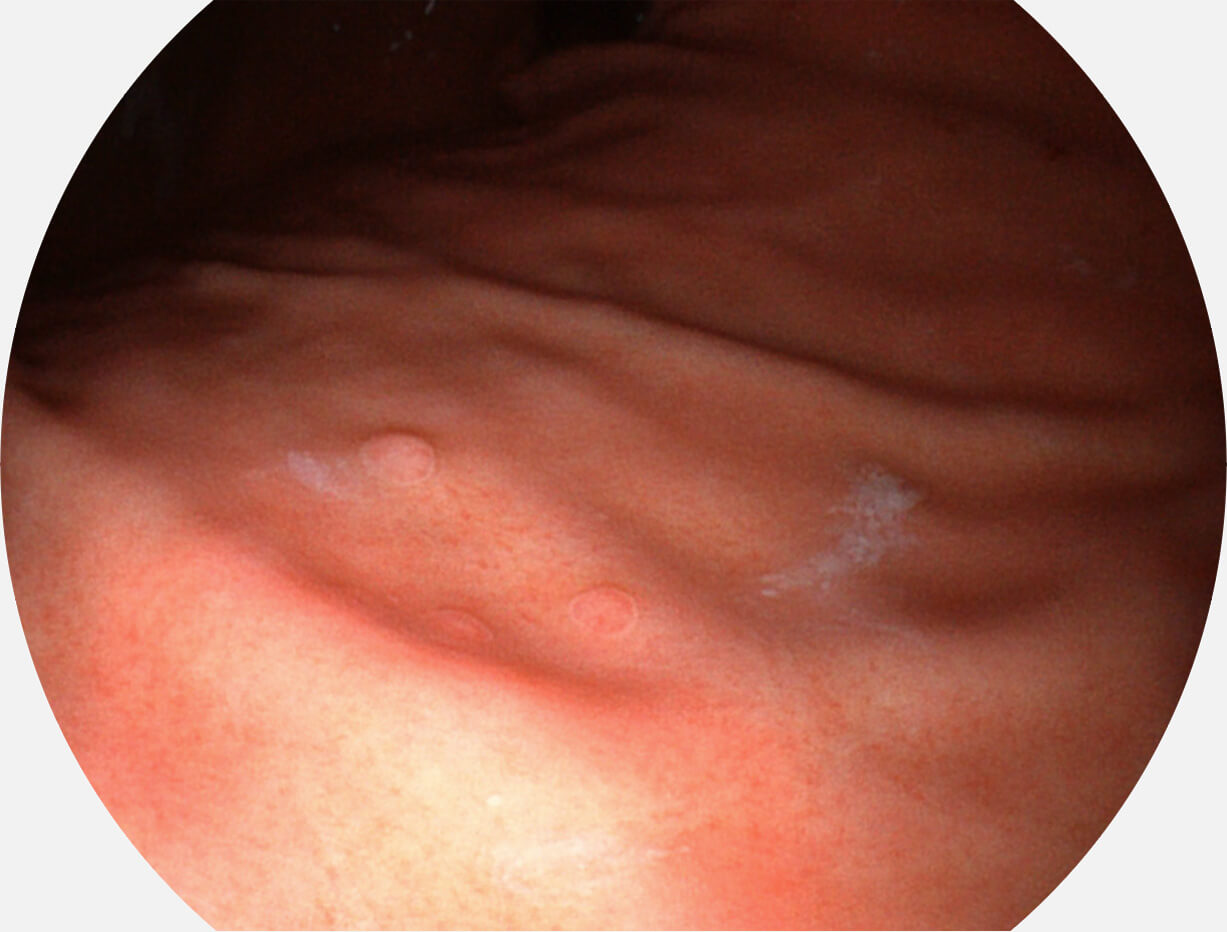

Versatile Intelligent Staining Technology, VIST

强调浅层黏膜结构的同时,保证照明亮度和提升浅层微血管与中层血管颜色对比度,病变边界更清晰。

白光图像

VIST图像

采用光路合束技术,光谱自由度高,实现了更丰富的照明模式,染色模式SFI及VIST,从远景到近景,助力消化道早期疾病诊断。